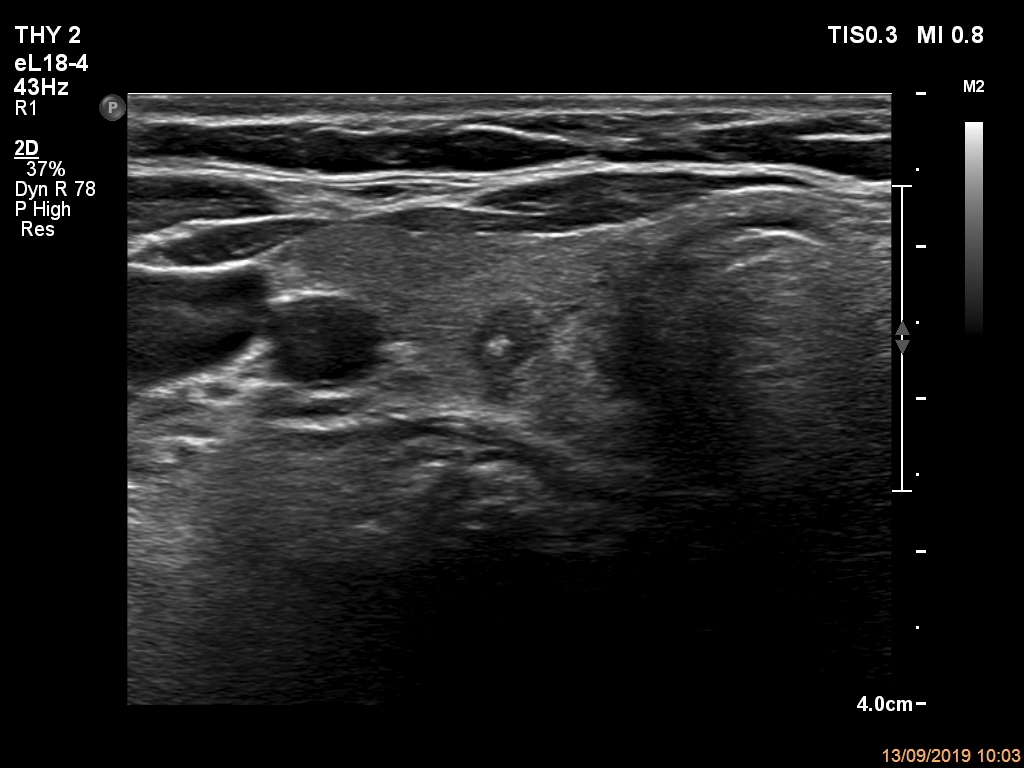

Ultrasonography. The thyroid was echonormal. There was a small hypoechogenic lesion in the central part of the right lobe. The lesion had microcalcification and non-parallel orientation, presented both taller-than-wide and taller-than-long shape. The left lobe had a hypoechogenic mass composed of discrete lesions. The whole mass displayed undulated margins which corresponded to non-pathological lobulation. On the other hand, a lesion within the mass had pathological, spiculated margins.